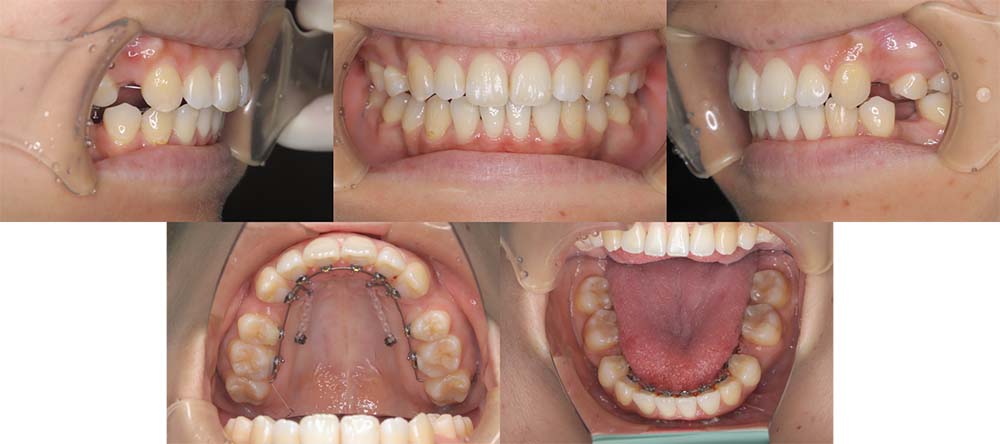

| 症例分類 | 上顎前突、口唇突出 |

| 診断名 | 左下4先天欠損を伴う上下前歯部叢生と骨格性上顎前突 |

| 主訴 | 出っ歯、下の歯がガタガタ、乳歯が1本ある |

| 年齢 | 31歳4ヶ月 |

| 性別 | 女性 |

| 抜歯部位 | 上の左右第一小臼歯と右下第二小臼歯と左下第二乳臼歯(4本) |

| 使用装置 | 上下裏側のワイヤー装置 |

| 治療期間 | 2年9ヶ月 |

| 保定装置 | 固定式保定装置、取り外し式保定装置(8時間) |

| 費用 |

[検査・診断料] ¥49,500 [基本施術料] ¥1,331,000 [調整料] ¥5,500/回 [抜歯] ¥5,500/本 [保定装置] ¥55,000(税込) 抜歯や虫歯治療は他院にて費用が別途かかります。(抜歯¥4,000〜10,000/本)

左下の永久歯が先天欠損で子供の歯が残っていて、その歯が抜けそうになったこともあり、矯正治療を考えて来院されました。

上下叢生と口唇閉鎖不全のため上下の抜歯をして治療をしました。下顎左側乳歯を抜去して治療をしました。

歯の動きが少しゆっくりだったため、予定より治療期間が伸びてしまいましたが問題なく咬合させることができました。